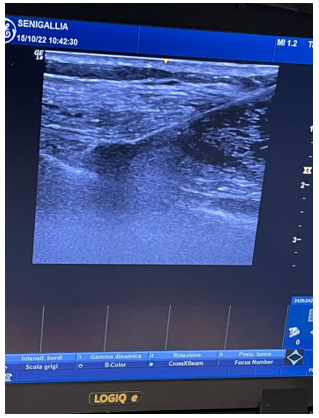

Figure 3: Ultrasound-Guided Approach to the Superior Medial Geniculate Nerve